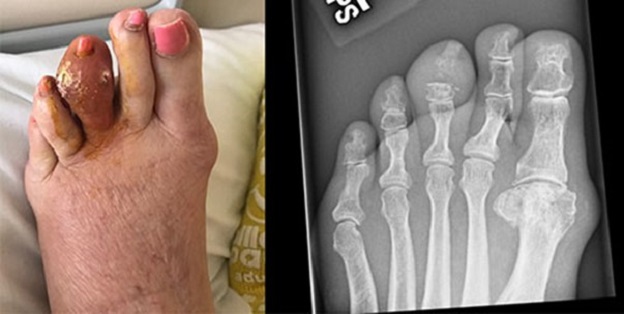

نقرس نوع دردناکی از آرتروز است. زمانی که اوریک اسید اضافی در بدن وجود داشته باشد، ممکن است کریستال های نوک تیزی در شست پا و دیگر مفاصل ایجاد شوند که منجر به تورم و درد خواهند شد. نقرس با کمک دارو و تغییر در رژیم غذایی و سبک زندگی قابل درمان است.

پزشکان نقرس را جزء زیرمجموعههای آرتروز دستهبندی میکنند که متشکل از یک طیف گسترده از بیماریها و درد مفاصل میشود. انواع مختلف آرتروز ممکن است باعث التهاب مفصل گردند، در حالیکه برخی دیگر این تأثیر را ندارند. نقرس یک نوع شائع از آرتروز التهابی است که بهوسیله کریستالهای اوریک اسید ایجاد میشود.

نقرس باعث درد و تورم در یک یا چند مفصل شما ازجمله زانو، مچ پا، مچ دست، کف پا، کف دست و آرنج خواهد شد ولی بیشتر انگشت شست پا را درگیر می کند.

گاهی اوقات ممکن است بدن مقدار زیادی اوریک اسید تولید کند یا کلیهها توان دفع کافی آن را نداشته باشند. زمانی که سطح اوریک اسید در بدن افزایش مییابد و به اصطلاح بدن دچار هایپراوریسمی میشود، ممکن است کریستالهای اوریک اسید در مفاصل جمع شوند. این کریستالهای تیز و سوزنمانند باعث ایجاد نقرس میشوند. البته، بسیاری از افراد با سطح بالای اوریک اسید به نقرس مبتلا نمیشوند.

نقرس توفوسی مزمن ناتوان کننده ترین نوع این بیماری بوده که باعث آسیب دائمی به مفاصل و کلیه ها می شود. در این مرحله فرد ممکن است به آرتروز مزمن دچار شده و این بیماری نواحی خنک تر بدن مثل مفاصل انگشتان را درگیر کند. نقرس توفوسی معمولاً پس از سال ها حملات حاد این بیماری ایجاد می شود و بروز آن در افرادی که درمان مناسب دریافت می کنند نادر است.

- توفوس: توفوس ها توده هایی از کریستال های اورات هستند که در زیر پوست تجمع پیدا می کنند. این توده ها می توانند اکثر مفاصل و غضروف ها ازجمله انگشتان، دست ها و پاها را درگیر کنند. توفوس ها به طور شایع بر روی گوش ایجاد می شوند. این تودهها ممکن است باعث درد نشوند ولی در صورت عدم درمان می توانند به مفاصل، استخوان ها و غضروف ها آسیب وارد کنند.

- آسیب و بدشکلی مفاصل: ابتلا به نقرس مزمن به معنی تورم منظم مفاصل خواهد بود. التهاب مزمن و توفوس ها می توانند باعث آسیب دائمی مفاصل، بدشکلی و خشکی آنها شوند. در موارد شدید نقرس مزمن ممکن است ترمیم مفصل نیازمند عمل جراحی باشد.